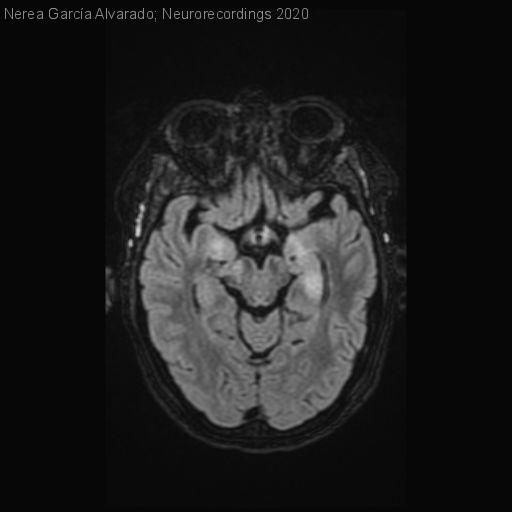

Diagnóstico final: Vasculitis del sistema nervioso central en paciente con Lupus sistémico (LES)

Neurología: Patología cerebrovascular

Etiología: Ictus | Autoinmune / sistémico

Mujer de 45 años con antecedentes de artritis asimétrica, presenta un cuadro agudo de afasia logopénica y hemiparesia derecha de predominio crural. Se realiza TAC multimodal sin signos de lesión isquémica aguda ni defectos de replección....